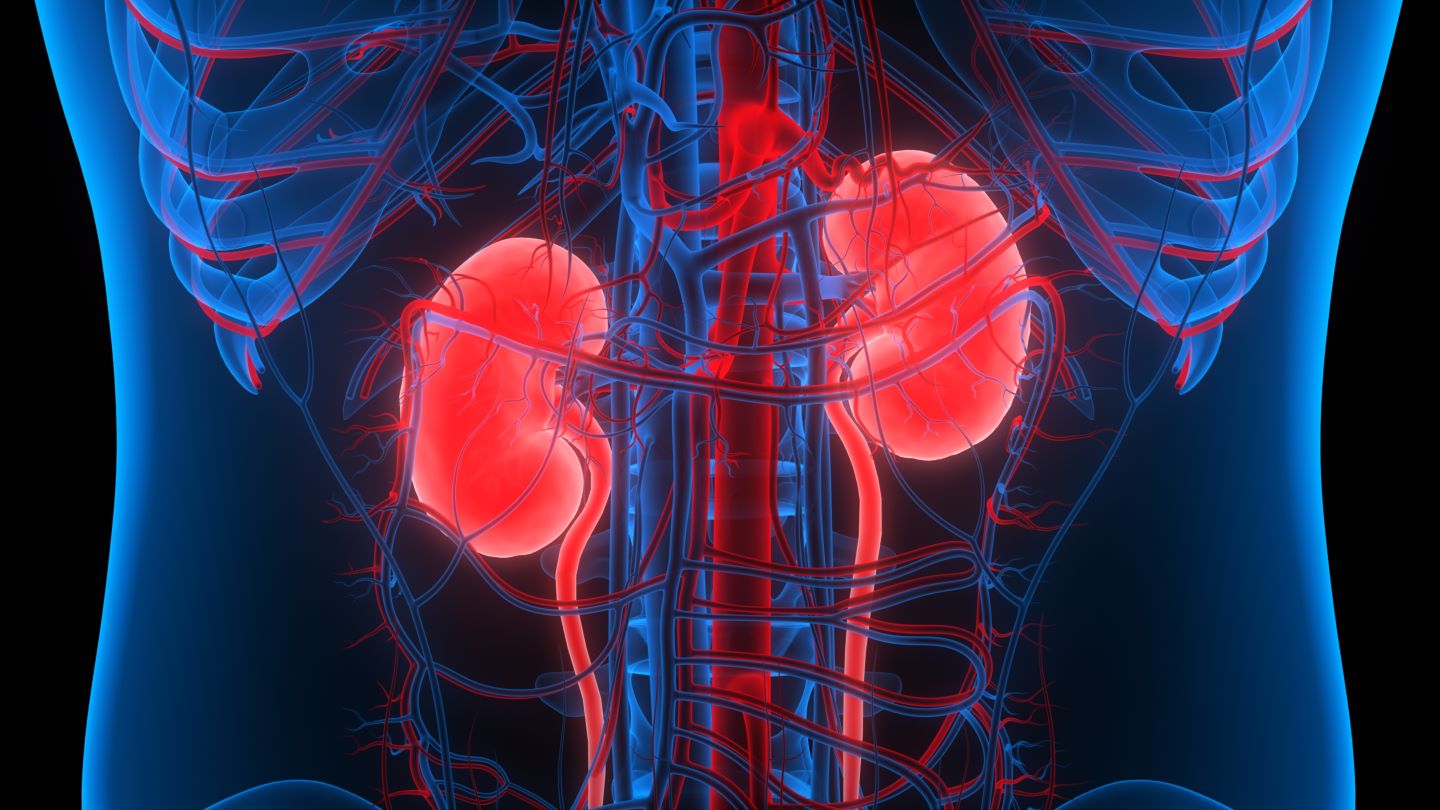

Строение почек человека: Фото и описание